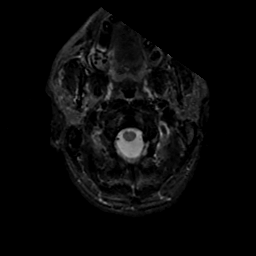

MR Study #17, July 7, 1991 -- Slice #1